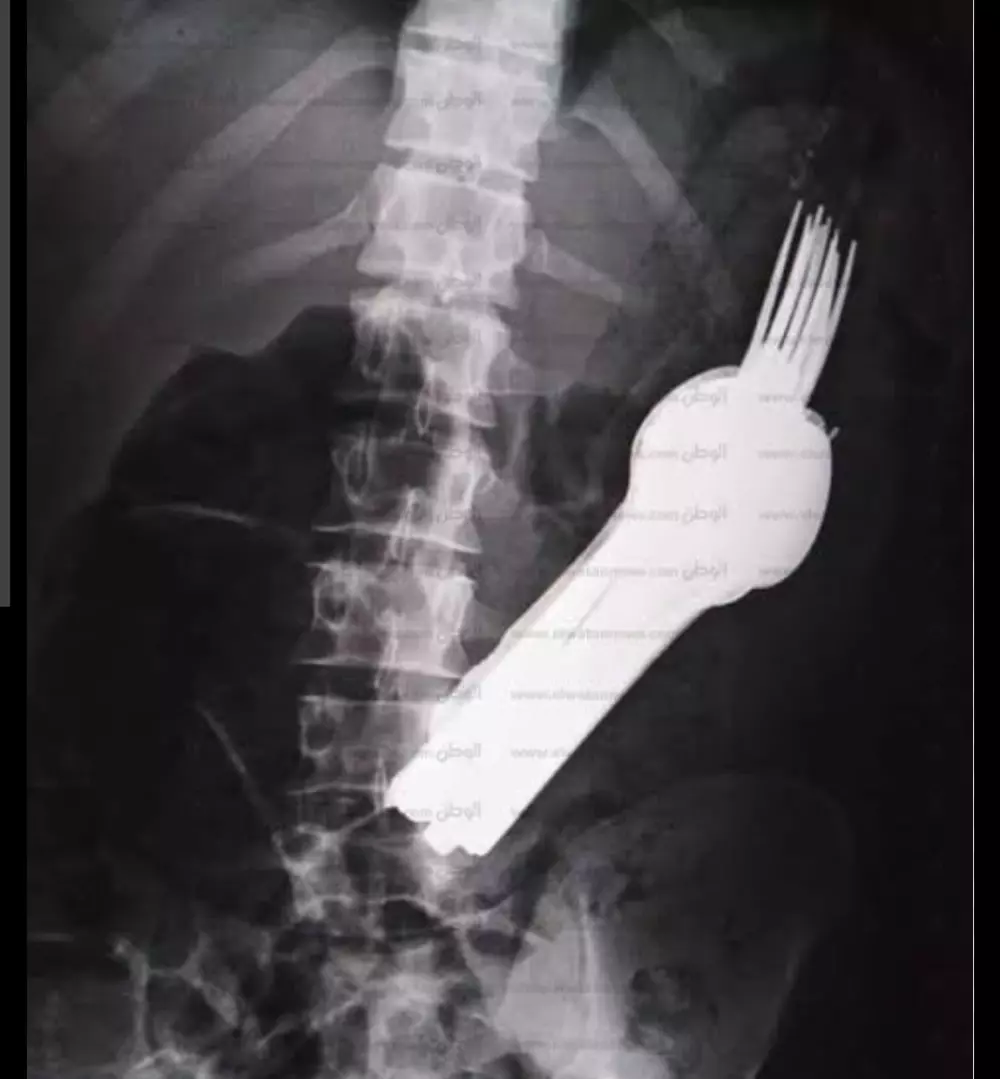

قراءة تقارير التحاليل والأشعه وتقديم ملخص ووصف استشاري عام دون تشخيص أو وصفه علاجيه وتوجيهك لزيارة الطبيب المختص ثمن قراءة تقرير التحليل 10 دولار لكل تقريرين والأشعه كذلك وإن كان هناك استشارات أو أسئله فسيكون ثمن ال5 أسئله 10 دولار ونؤكد على أن المعلومات المقدمه لا تغني عن زيارة الطبيب ولا تعتبر تشخيص نهائي ولا أصف لك دواء فقط اطمئنك على حالتك عوفيتم